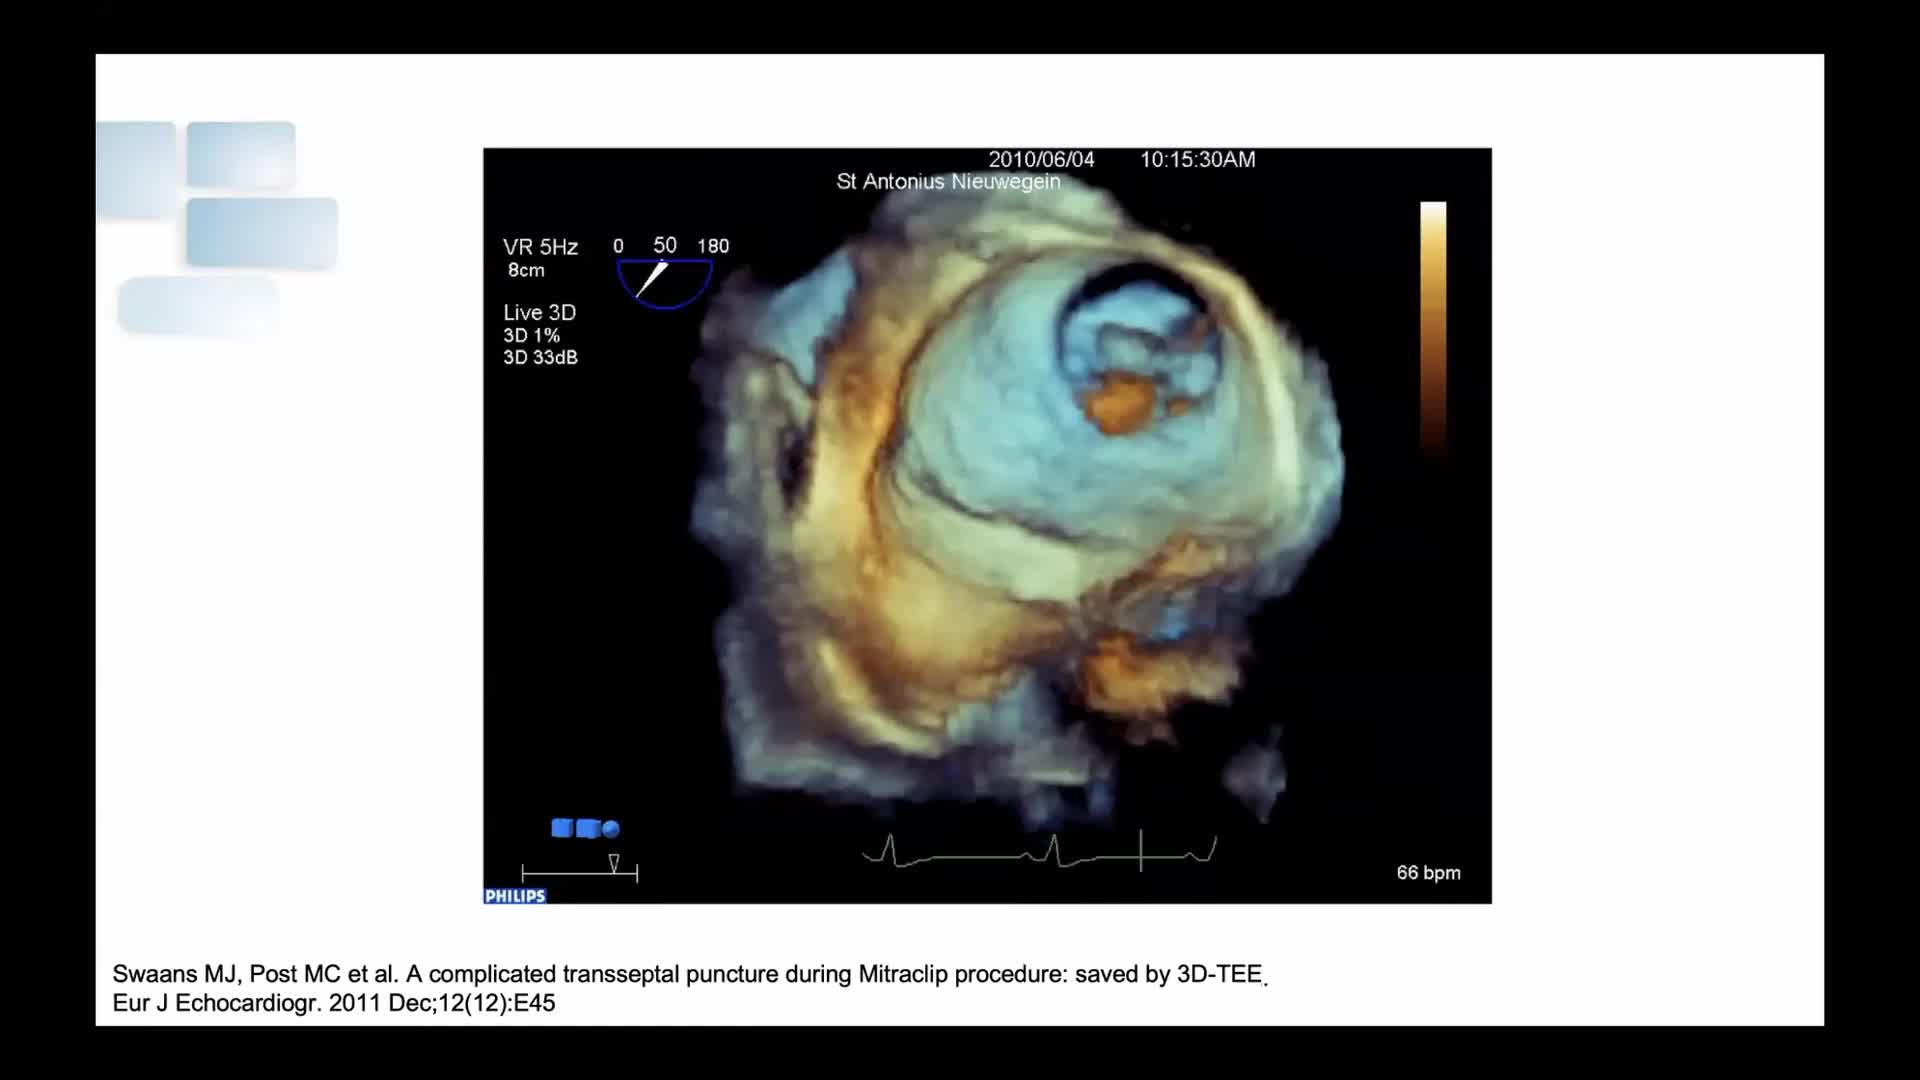

CSI CATHLAB LIVE - INTER-ATRIAL SHUNT FOR DECOMPRESSION OF THE LEFT ATRIUM IN A PATIENT WITH VERY SEVERE HEART FAILURE WITH THE AFR DEVICE